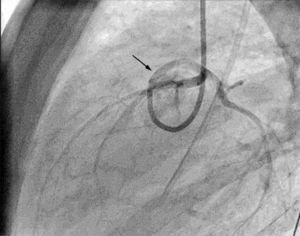

Se decide realizar coronariografía, objetivándose el origen anómalo de la ACI en el seno coronario derecho (fig. 1) con trayecto intraarterial.

Figura 1. Coronariografía. Origen y trayecto anómalo de la coronaria izquierda (flecha negra).